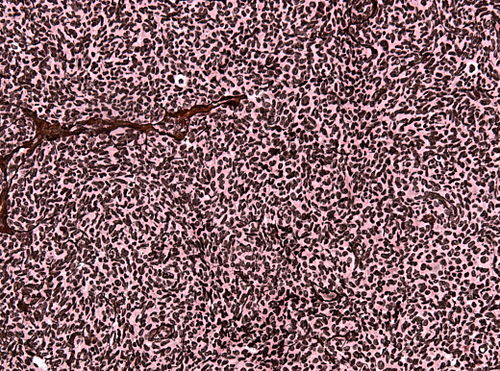

45 year old male with visual acuity disturbances

Site

Occipital lobe

Intermediate magnification. H&E stain.

I spot very few brown pigments that need to be examined more closely.

| HMB-45 | Very few cells POSITIVE |

| MITF | Very few cells POSITIVE |

| S-100 | POSITIVE |

| BRAF sequencing | V600E mutation present |

Metastatic malignant melanoma, BRAF V600E mutated